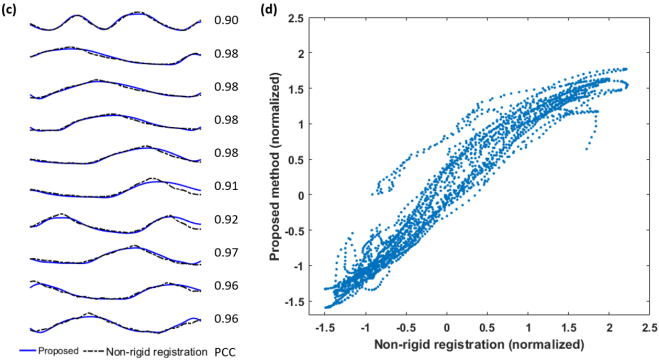

Using the extracted respiratory signal as a guide, we extracted one end-inspiration (EI) and one end-expiration (EE) heartbeat from each slice for one of the volunteers. Fig. 4 shows data separated into EE and EI heartbeats. All slices within EE have, as expected, elevated liver dome compared to the corresponding EI slices. However, a significant in-plane and through-plane motion of the heart can be noticed between EE and EI, highlighting the perils of mixing slices from different respiratory phases.